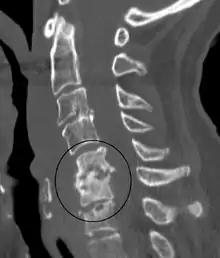

![]() التهاب القرص عند طفل يبلغ عمره سنتين. التهاب القرص عند طفل يبلغ عمره سنتين. | |